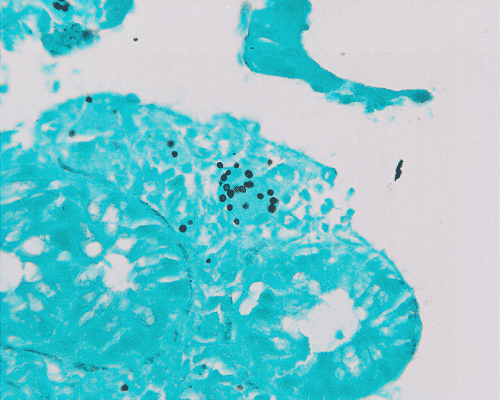

On low-magnification, the biopsy appears to be a piece of colonic mucosa without evidence of necrosis, erosion, or ulcer (Panel A). On medium-magnification, the lamina contains some vaguely formed collections of large cells (Ú in Panel B). On high-magnification, there are many large, round cells with eccentric nuclei. These are macrophages in clusters that are consistent with granulomas.  Many small, grayish to basophilic, vesicle-like structures are present in the cytoplasm (Panel in C). In other areas, these large, round cells do not really form small clusters and are admixed with lymphocytes (Panel D). Again, many small, grayish vesicle-like structures are present in these cells. A grayish to basophilic core is present and is surrounded by halo (Ú in Panel E).  These structures are most suggestive of microorganisms particularly fungus. On periodic acid Schiff (PAS), these vesicles appear bright purple-red (Panel F and G). The basophilic core is also strongly positive for PAS stain (Panel G). These microorganisms appear dark with Gomori methamine silver stain (Panel H and I).

In immunocomprised patients that have defective cellular immunity, granuloma formation may be rather indistinct as illustrated in our case. The yeast form of Histoplasma capsulatum is found in tissue and they are usually under 5 mm in diameter and appear as ovoid yeasts.  The lung is the most affected organ. Granuloma formation, typically multiple, with extensive caseous necrosis and a variable amount of calcifications are the typical pathologic changes in the lung. These granulomas are often demarcted from the surrounding tissue by a fibrous wall. Granulomas in the lung can get quite calcified with time. The pulmonary nodules can also enlarge slowly to give a wrongful clinical impression of neoplasm, the so-called histoplasmoma. The living yeast in tissue, often occur in clusters, has a basophilic center and a translucent halo that represents the capsule. They are often engulfed by histiocytes as illustrated in this case. Dead organisms appear eosinophilic and cannot be detected easily in granuloma by hematoxylinj-eosin stain. The microorganism is numerous and can be identified on routine hematoxylin-eosin stain with astute observation and high index of suspicion. Typically, there are numerous yeasts and they are present even in heavily calcified nodules or granulomas.

H. capsulatum, like many other fungal organisms, are well demonstrated by periodic acid Schiff (PAS) stain, Gomori’s methamine silver (GMS) stain, and other appropriate stains in tissue. Although the size and shape can suggest Candida species, there is no pseudohyphae formation in H. capsulatum which allows the distinction. They also lack the paired dense capsular thickening as in Pneuocystis carinii. Coccidiodes immitis form large endospores which allow separation from H. capsulatum. [Click here to see a picture of C. immitis with GMS stain]